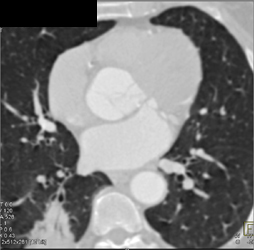

Diagnosis

Dilatation of RCA